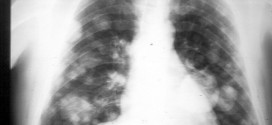

Leer MásTUMOR DE PULMÓN METASTÁSICO

El tumor de pulmón metastásico. Los pulmones son un par de órganos que dan oxígeno al cuerpo y expulsan el dióxido de carbono, un producto de desecho producido por las células del cuerpo. Los bronquios, por su parte, son unos tubos a través de los cuales llega el aire inspirado desde la boca a los pulmones; se dividen en otros …

Leer MásCÁNCER METASTÁSICO PULMONAR

El cáncer metastásico pulmonar. Los pulmones son dos órganos situados en el tórax y a través de ellos se realiza la respiración. Están separados por una zona denominada mediastino, espacio donde se encuentran el corazón, la tráquea, el esófago y vasos sanguíneos. El aire llega a los pulmones a través de la tráquea que se divide en dos bronquios principales, …

Leer MásCANCER METASTASICO DE PULMON

El cáncer metastásico de pulmón. Durante los primeros años de vida de una persona, las células normales se dividen más rápidamente para permitir el crecimiento. El cuerpo está compuesto por billones de células vivas. Las células normales del cuerpo crecen, se dividen formando nuevas células y mueren de manera ordenada. Una vez que se llega a la edad adulta, la …